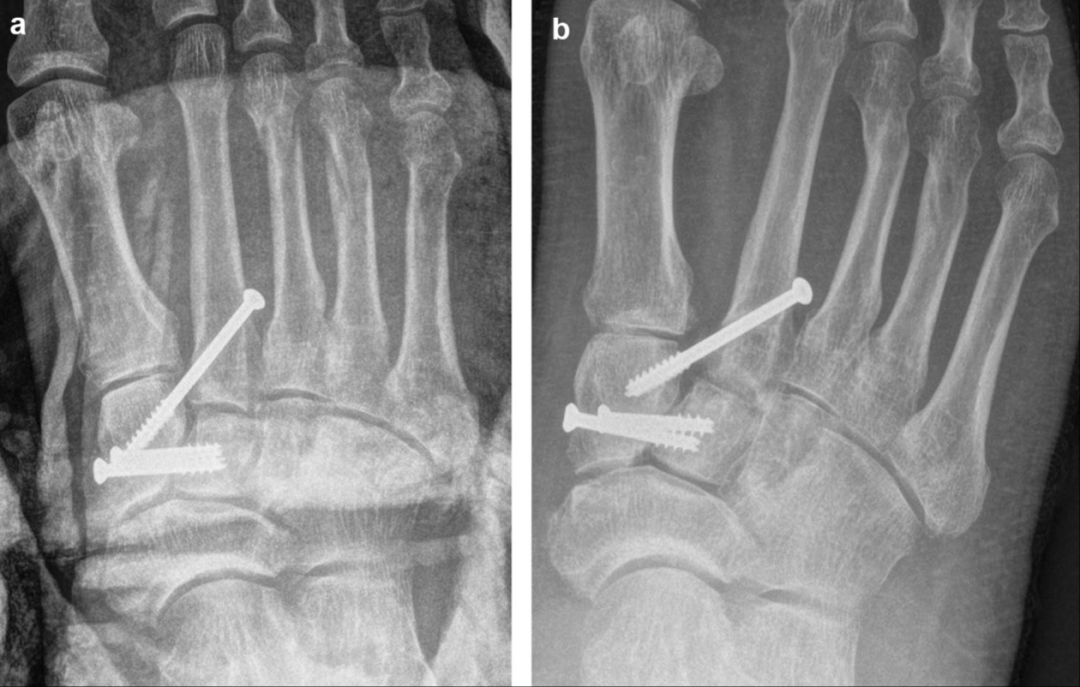

一例采用逆行Lisfranc螺钉(4.0mm部分螺纹空心螺钉)治疗的术后即刻(A)和术后7个月随访(B)足正位放射片,出现复位丢失。